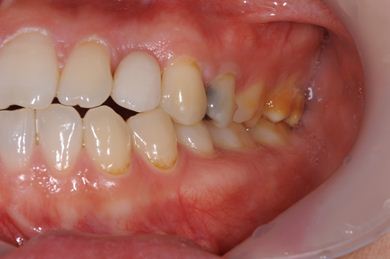

治療前

• 治療前